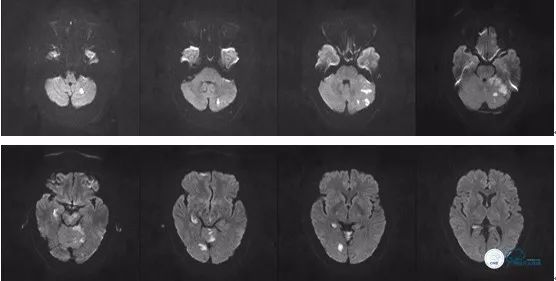

术后头颅MR DWI序列:

图14

图15

术后第5天出院,出院时NIHSS评分0分,生命体征平稳。